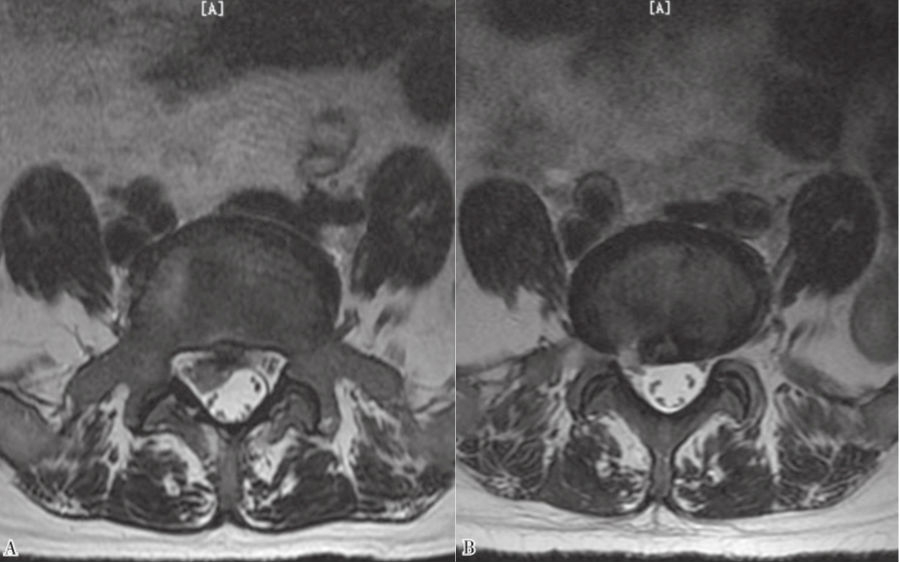

9. 术后复查MRI。(图43、图44)

图43 术前和术后MRI轴位对比

A. 术前腰椎MRI轴位;B.术后腰椎MRI轴位

图44 术前和术后MRI核磁共振矢状位对比

A. 术前腰椎MRI矢状位;B.术后腰椎MRI矢状位